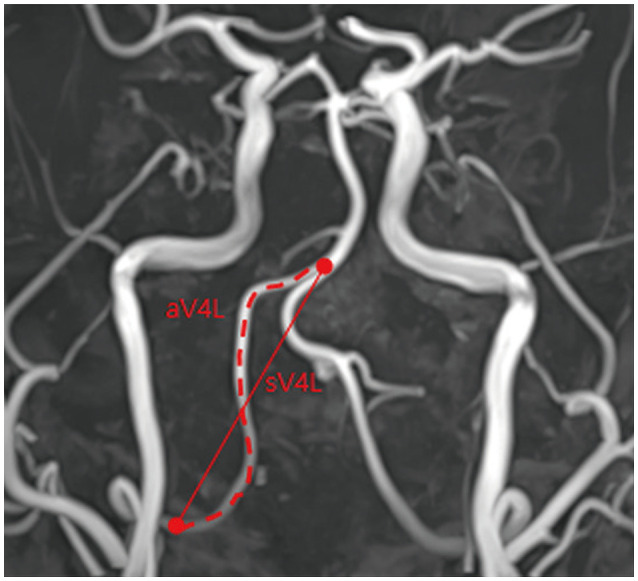

Methods: This observational study was carried out at a single center and included patients who had been diagnosed with iVADA based on neuroimaging findings. We divided the patients into two groups: with and without iVADA growth. Growth was defined as any enlargement of a dilated region or a morphological change in follow-up imaging. We measured the vertebral artery tortuosity index (VTI) in the contralateral vertebral artery (VA), defined as its actual length divided by its straight length. We investigated the factors associated with iVADA growth.